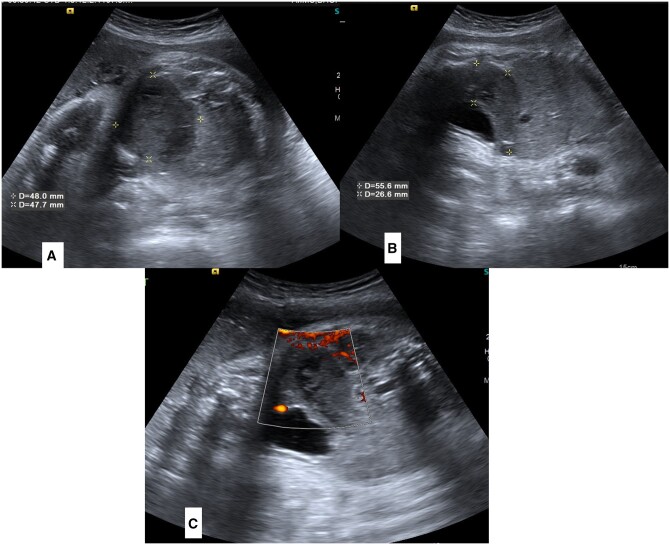

Congenital pouch colon (CPC) is highly uncommon congenital anorectal malformation where a distended pouch-like structure replaces either some part of the colon or the entire colon and communicates to the genitourinary tract through a fistula. Diagnosis of CPC is usually made after birth when neonate/infant presents with abdominal distension and absence of anal opening. Making antenatal diagnosis of CPC is difficult because of the lack of specific and verifiable signs on sonography. Hence, only a few cases of antenatal diagnosis of CPC have been reported.1,2 In our case, CPC was suspected on a routine antenatal growth scan ultrasound in the late third trimester, showing a hypoechoic tubular-shaped lesion in the pre-sacral region. With this suspicion, we suggested an institutional delivery at a tertiary level centre, and diagnosis of type III CPC was confirmed on post-delivery imaging and emergency primary surgery, done on the day 3 of life (pouch resection, division of fistula, and protective colostomy). The child also underwent further corrective surgeries in a staged manner in second year of life and recovered completely. Beforehand diagnosis prevented any unnecessary delay in operative care, reduced postoperative complications, and improved the overall outcome of this otherwise complex condition.